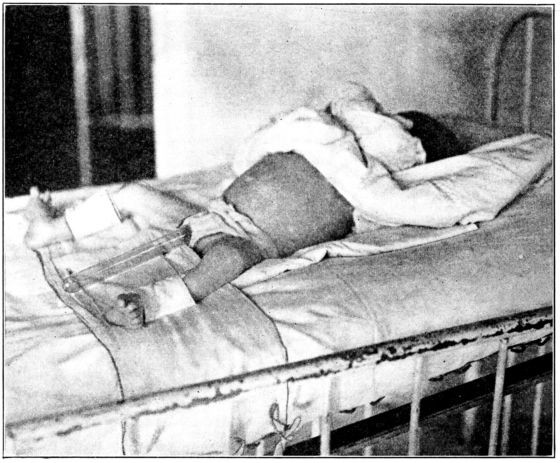

| 49. | Method of giving infusion | 202 |